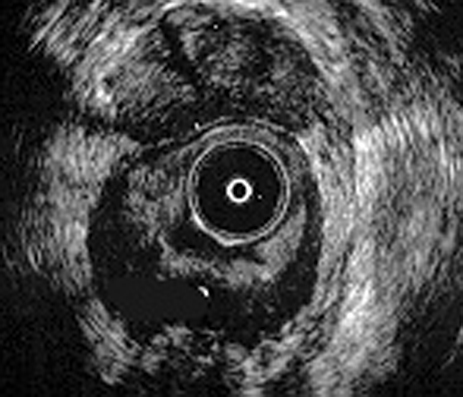

Ecografía anal por encima elevadores. Próstata anterior. Gran absceso supraelavador